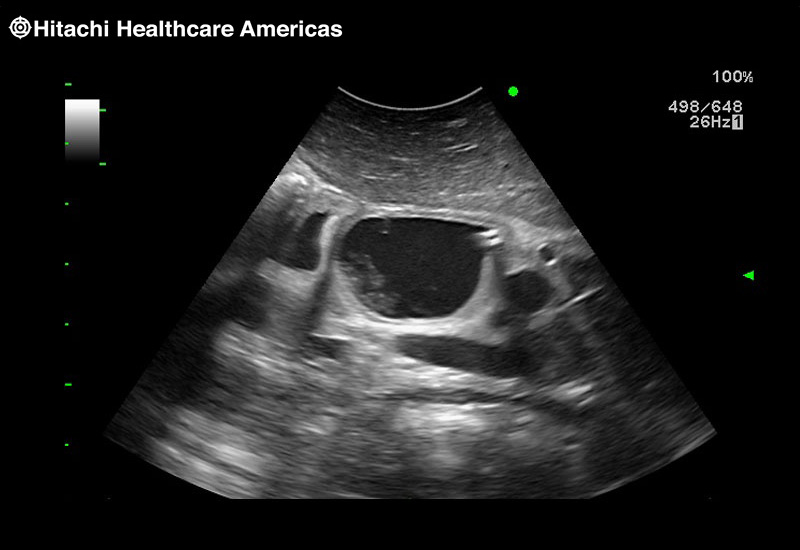

Superior guidance for all applications

Fujifilm Healthcare Americas is committed to designing tools that help surgeons navigate inside the human body and provide the necessary information to immediately make critical surgical decisions.

Fujifilm Healthcare's dedication to Surgeons provides outstanding ultrasound technology, professional support and the specialized tools necessary to best perform comprehensive real-time ultrasound imaging in Breast Surgery, General Surgery, Laparoscopic Surgery, Neurosurgery, Robotic Surgery and Surgical Oncology.

The Arietta 65 has many advanced and unique probes that fully cover the expanding range of procedures that benefit from ultrasound guidance.

The Arietta 65 has many advanced and unique probes that fully cover the expanding range of procedures that benefit from ultrasound guidance.

Imaging Clearly Defined

State-of-the-art digital architecture and advanced imaging features to redefine the capabilities of surgical ultrasound.